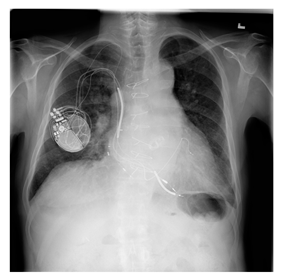

- (c)

- NIH Database

ANIH is an X-ray type image database collecting chest medical images. Some samples are shown in Figure 12c.

Figure 12.

Sampled images in the tested benchmark databases: (a) Breast-MRI-NACT-Pilot (breast), (b) ACRIN-DSC-MR-Brain (brain), (c) NIH (chest), (d) Lung-PET-CT-Dx (lung), (e) Prostate-MRI (prostate), and (f) Other grayscale standard images.